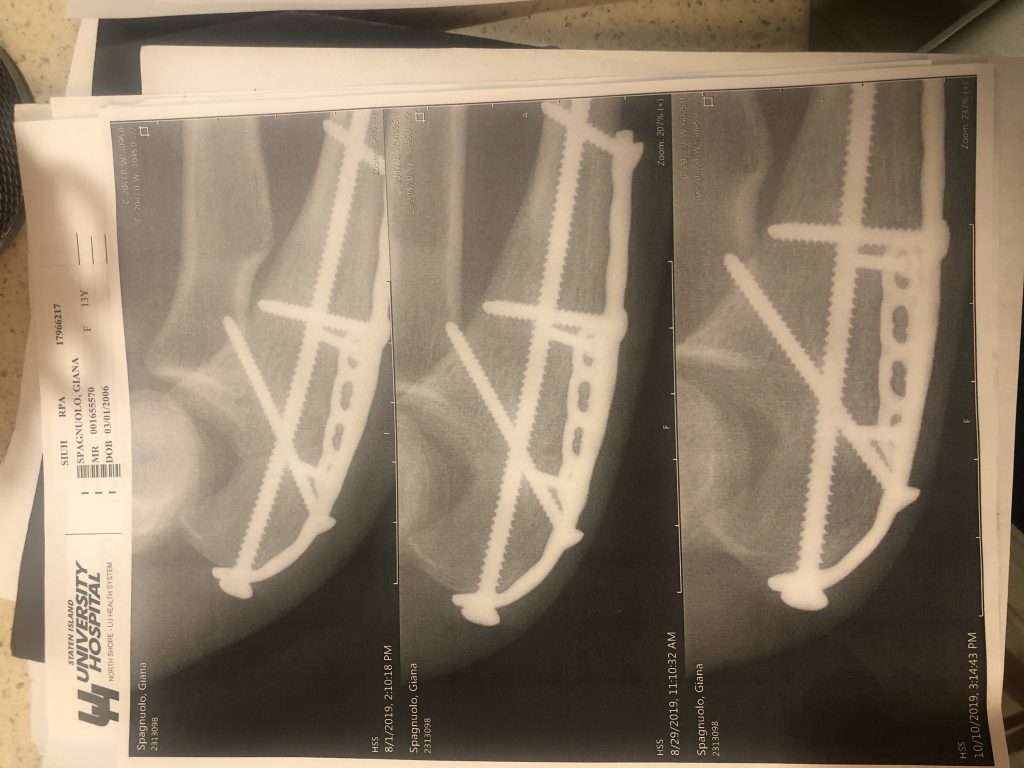

It was our first day of vacation in the Poconos with family on July 15, 2019. My cousin and I went out for a ride in the golf cart and a sharp turn going from the paved road to a gravel path sent me flying onto the pavement. My elbow broke my fall and the force broke my olecranon bone. I found out immediately that this would require surgery from someone who specializes in this. I was referred to HSS and Dr. Fabricant. They fit me into his busy schedule within a day. He knew that I just couldn’t wait and my 4 hour surgery required 2 plates and eight screws to correct. Because I am a dancer and member of the color guard in marching band he understood how important it was for me to have the best possible outcome and that is exactly what I got. After my follow up visits, multiple braces tailor made to fit me through every stage of my recovery and physical therapy, I was back to my usual activities within 6 months. I was able to participate in marching band season and perform with my dance groups. 18 months after surgery in February 2021 I had a follow up surgery in which Dr. Fabricant removed all of the plates and screws. I am so grateful for the attention and professional care from my physician and the hospital staff who treated me.